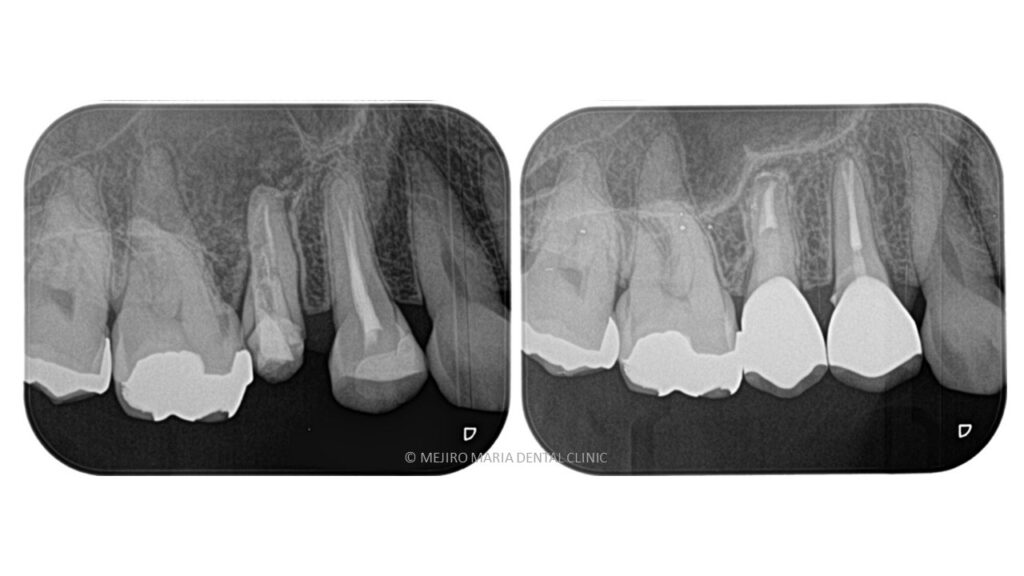

この患者様は、前医での根管治療がうまく行っていないことを主訴に当院の精密根管治療カウンセリングを受診されました。初診時の段階で歯肉の炎症が著しく、根尖部を指で押すと痛みを訴えておられました。診査したところ右上5番の根尖には黒い透過像(写真2黄色囲み線)が確認できるのと、歯質は大きく削られており(写真2赤線部)、残存する歯質は(写真2青線部)非常に薄くなっていることが確認できました。

初診の時点では破折等の所見は確認されなかったことら、治療は可能と判断しましたが、歯質が薄いことから将来的な費用対効果が低くなることも考えられました。

精密根管治療終了後、3ヶ月間仮歯で症状の経過を確認し、予後良好と判断して最終補綴物へ移行しました。

経過2年の段階で根尖に確認できた根尖性歯周炎は縮小し、予後良好の経緯を確認しています。